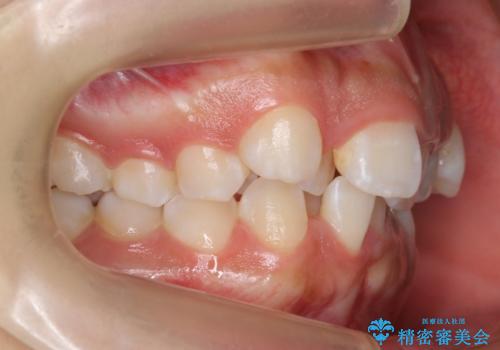

前歯のがたがた 前歯が内側に傾いている

- 前歯のがたがたを主訴に来院。

上の歯並びが前にずれて、さらに前歯が内側に倒れて過蓋咬合を呈していました。

奥歯のかみ合わせもずれていたため、上の奥歯を後ろに下げる処置をミニスクリューを用いて行いました。